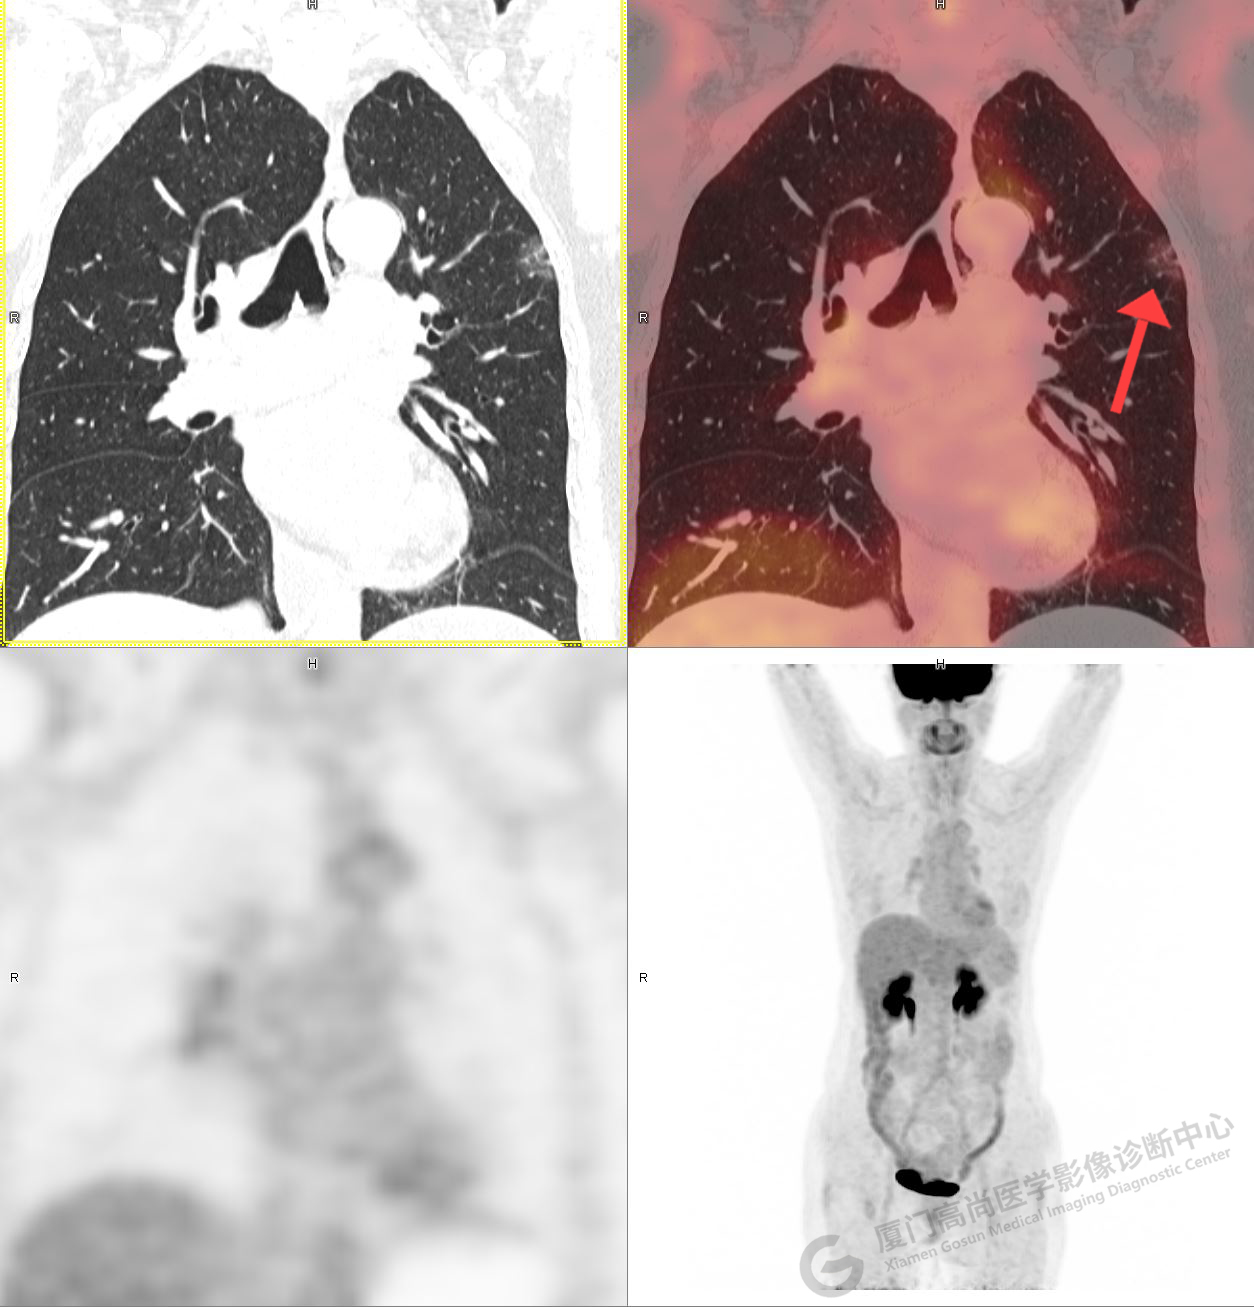

PET/CT影像圖

圖1

圖2

PET/CT示:右肺下葉結(jié)節(jié),代謝增高,考慮為周圍型肺癌,建議穿刺活檢。

病理證實(shí)是肺腺癌。